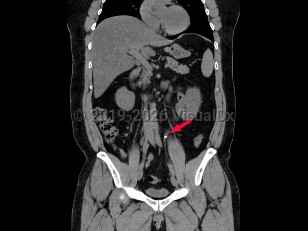

Ureteral calculus